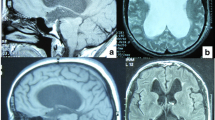

Computerized tomography (CT) is the best means to offer easily available, fast, reliable, and reproducible imaging of the ventricles of the brain. Different investigations can be easily compared. Children often do not have to be sedated. Therefore, CT is ideal for follow-up of ventriculomegaly or its treatment after 1–2 years of age and especially so in an emergency setting. CT may allow differentiation between different forms of hydrocephalus and differentiation of etiological factors, but not in sufficient detail. In occlusive hydrocephalus due to aqueductal stenosis, the fourth ventricle may be relatively small in comparison to the other ventricles. The size of the fourth ventricle, however, is not a very reliable sign in differentiating occlusive hydrocephalus from communicating hydrocephalus. For example, in case of a dilated fourth ventricle, one cannot differentiate between communicating hydrocephalus and fourth ventricle outlet obstruction due to congenital occlusions or to secondary infectious or hemorrhagic processes [17, 38].

Magnetic resonance imaging (MRI) reveals the most details of the brain and CSF pathways. It allows discrimination of obstructions and membranes, excavations of the ventricles, displacement of anatomical structures, anatomical variations, space-occupying lesions, etc. The constructive interference in steady-state sequence may especially help in delineating membranes and septa in CSF-containing spaces. Besides this, MRI is able to provide qualitative and quantitative information of CSF flow and dynamics [16, 40, 41, 45, 48, 52, 67]. The MRI study of CSF flow in and around the fourth ventricle can be more difficult because the fourth ventricle has three outlets [38]. On the other hand, MRI is usually not readily available, is more expensive, and often requires sedation or even narcosis of the child. Therefore, MRI is not ideal for follow-up diagnostics, but is best used for pretreatment classification of the hydrocephalus.

Therefore, classification of hydrocephalus becomes critical in predicting the result of an ETV. This requires more details of the hydrocephalus than only the presence of a dilated ventricular system with corresponding signs and symptoms, which might be sufficient to adequately perform a shunting procedure. The single most valuable investigation to obtain maximum information is MRI. Besides anatomical information it also may give information on CSF flow dynamics. No other investigation or combination of investigations will give as much detail as MRI. Nevertheless, additional investigations may add information to the MRI.

Fourth ventricle outflow obstruction, a condition than can be successfully treated by ETV, can be difficult to assess by MRI alone. In those cases, where fourth-ventricle outflow obstruction is anticipated or discussed, intrathecal contrast examination followed by CT scan might be helpful.